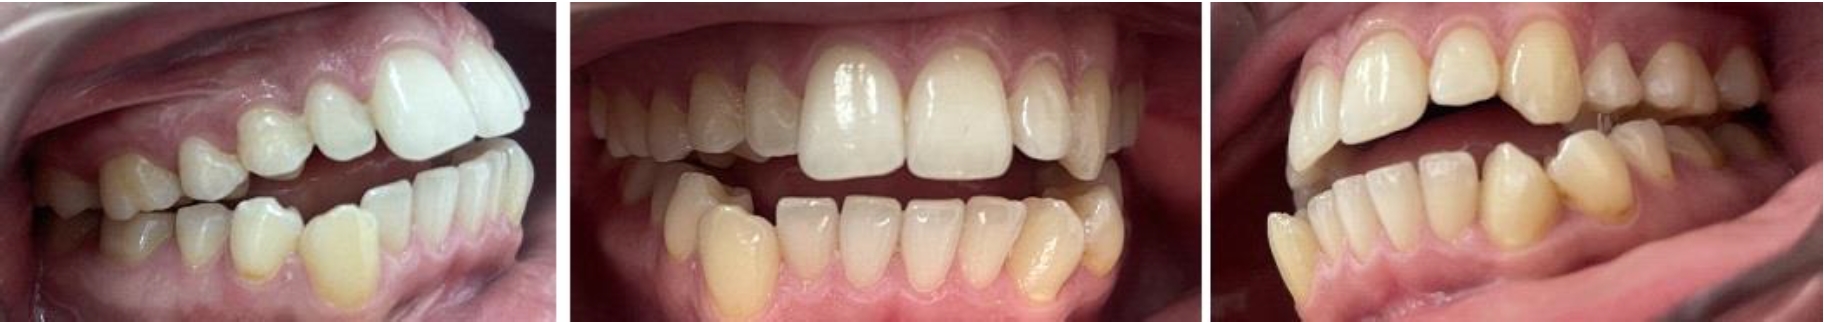

Анализ окклюзионного статуса показал наличие вертикальной резцовой окклюзии, смыкание моляров по второму классу, отсутствие врехнего правого клыка и верхнего второго премоляра, что и определяло укорочение верхней зубной и альвеолярной дуги. На нижней челюсти определялась скученность (краудинг) передних зубов и ротация клыков (рис. 3).

Рис. 3. Состояние окклюзионного статуса при гнатической форме дистальной окклюзии